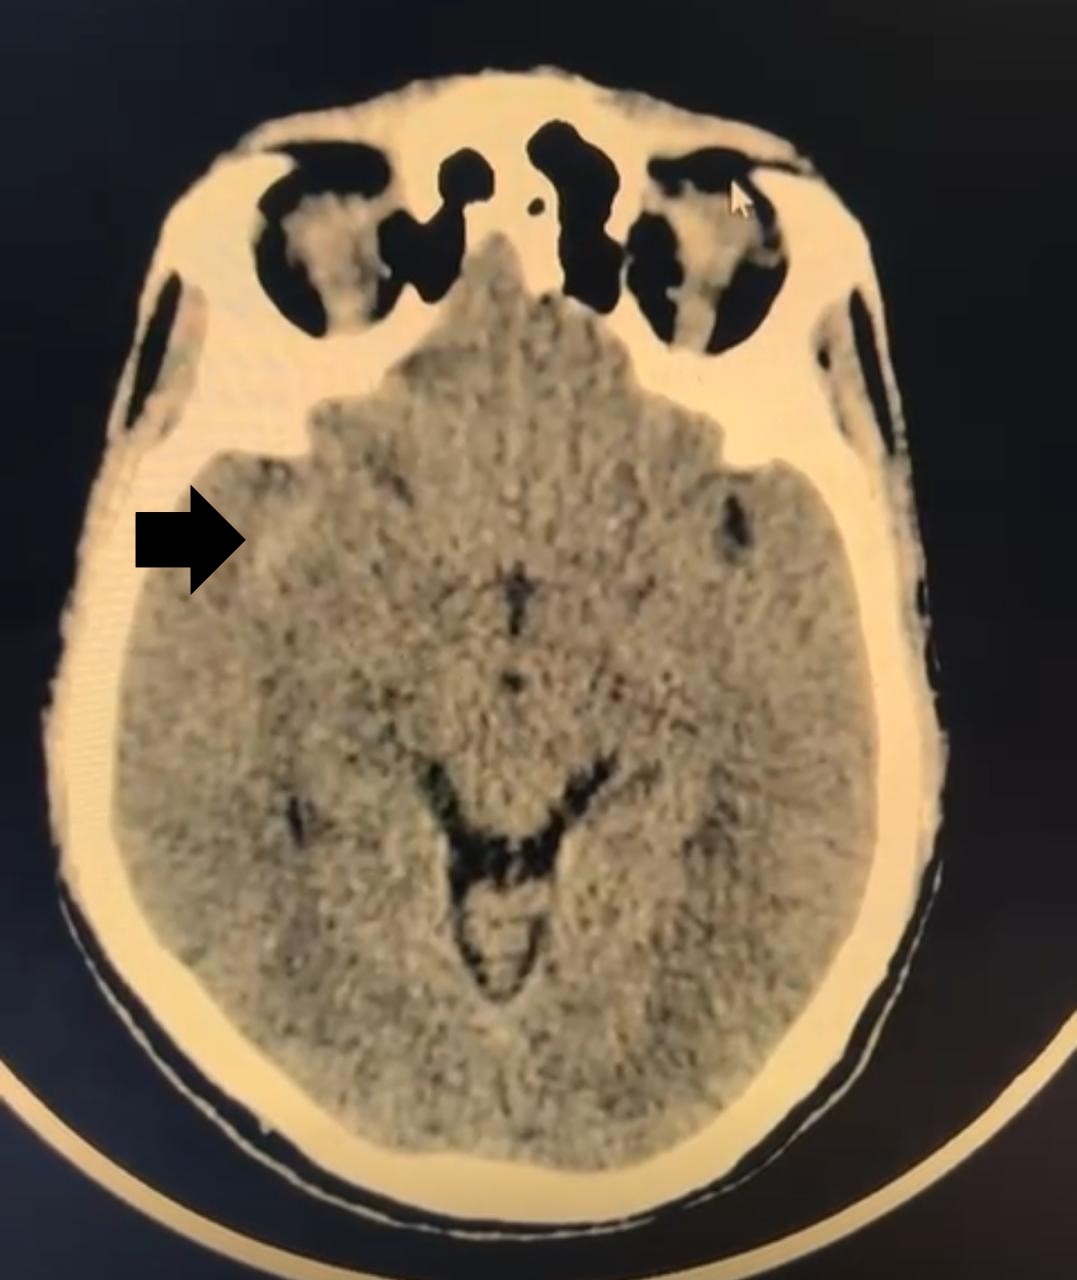

Non-contrast computed tomography (NCCT) of the brain revealed subarachnoid hemorrhage predominantly in the right sylvian fissure [Figure 1]. Hemorrhage grading scales indicated: Modified Fischer Scale 1, Classen Scale 1, and Hijdra Scale 0; indicating minimal blood burden with low risk for delayed cerebral ischemia and vasospasm. These favourable grading parameters not only suggested minimal vasospasm risk but also projected good functional prognosis.